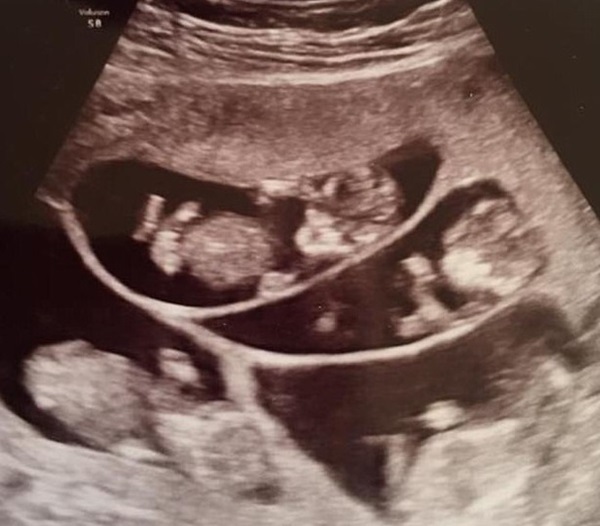

Hình ảnh siêu âm thai 7 của Bobbi